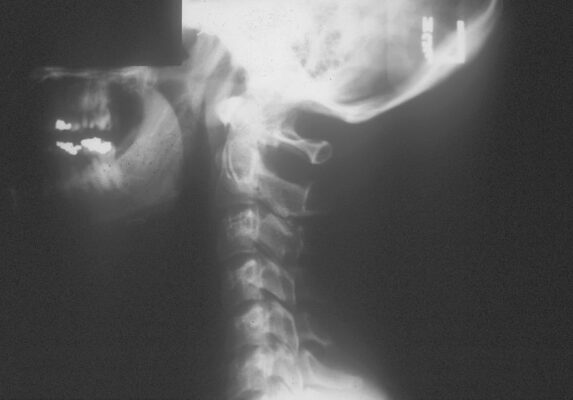

- Nên chụp X quang để loại trừ gãy xương ở những bệnh nhân bị chấn thương và những bệnh nhân có thay đổi ý thức (như say rượu), hoặc đau cột sống cổ và có các dấu hiệu thần kinh khu trú với giảm tầm vận động khi khám lâm sàng. Mặc dù phim chụp nghiêng có thể thấy mất đường cong ưỡn sinh lý, kết quả này có thể là do sự co thắt của các cơ cạnh cột sống cổ và không có ý nghĩa nào khác (Hình 4).